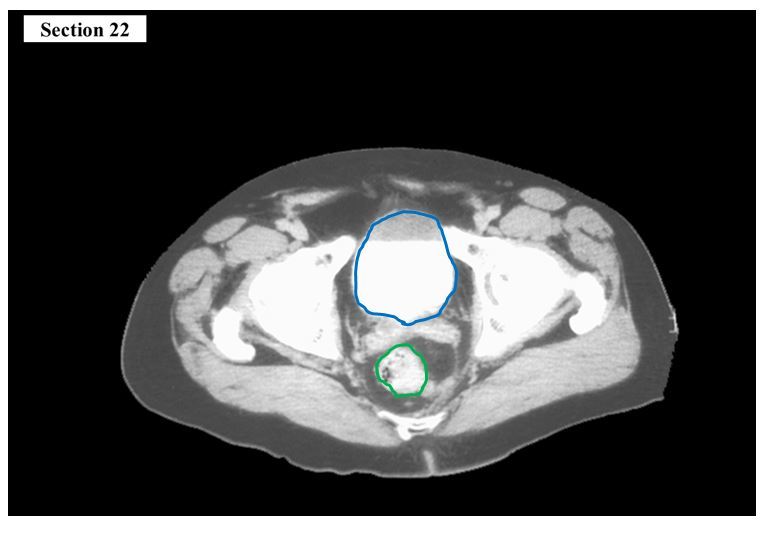

14

Q

The blue organ is the ___

The green organ is the ___

A

urinary bladder

rectum